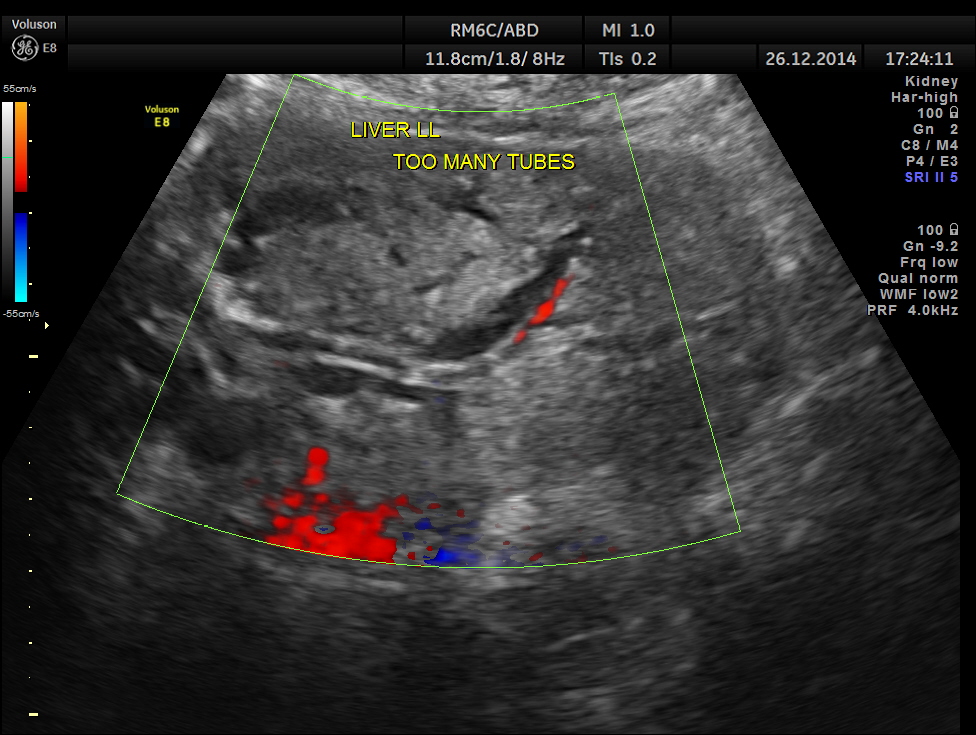

too many tubes seen in the left lobe of the liver.